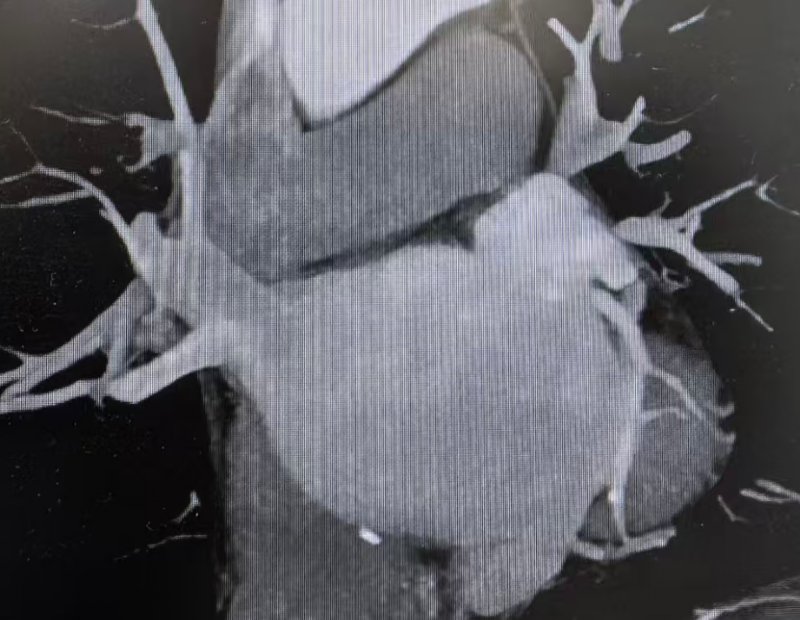

针对这一复杂病情,心血管内科系主任姜大明带领心律失常介入团队迅速开展多学科会诊。为确保手术安全与精准性,团队特邀李阳教授共同制定方案,并联合超声科1、CT科、麻醉科1等多科室提前做好术前准备:何昊医生与陈银凤医生通过食道超声检查,精准测量患者左心耳开口大小与形态,排除血栓隐患;CT科单世馨主任、马福成医生完成左心耳CT三维重建,清晰呈现解剖结构,为封堵器选型与手术路径规划提供“导航支持”。

食道超声及肺静脉CTV清晰呈现左心耳解剖结构